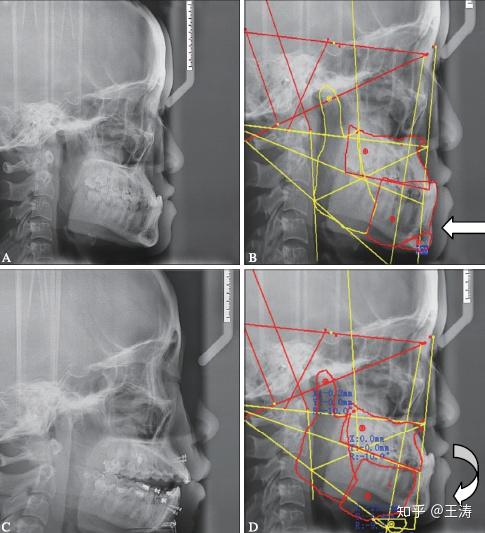

图 4典型病例3 该患者下颌spees曲线较深,术者按手术先行做了下颌

图片尺寸485x533

这两张图片已经很好的诠释了这样一个曲线是有利于上颌平面和下颌平面